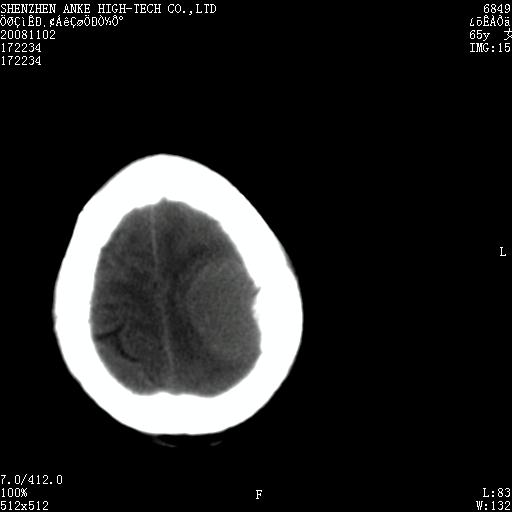

患者,女性,65岁,突发右侧肢体无力伴头痛,恶心、呕吐3小时.

1 左侧顶区圆形病灶,内可见钙化,考虑脑膜瘤,建议增强。2 左侧侧脑室病变,考虑神经上皮囊肿。

1)左侧顶区脑膜瘤可能性大;建议必要时行进一步检查。2)左侧脑室积水。

左顶部脑膜瘤,左侧侧脑室蛛网膜囊肿,建议增强.

左侧脑外占位(脑膜瘤)压迫脑实质、脑室侧室孔所致积水。支持!